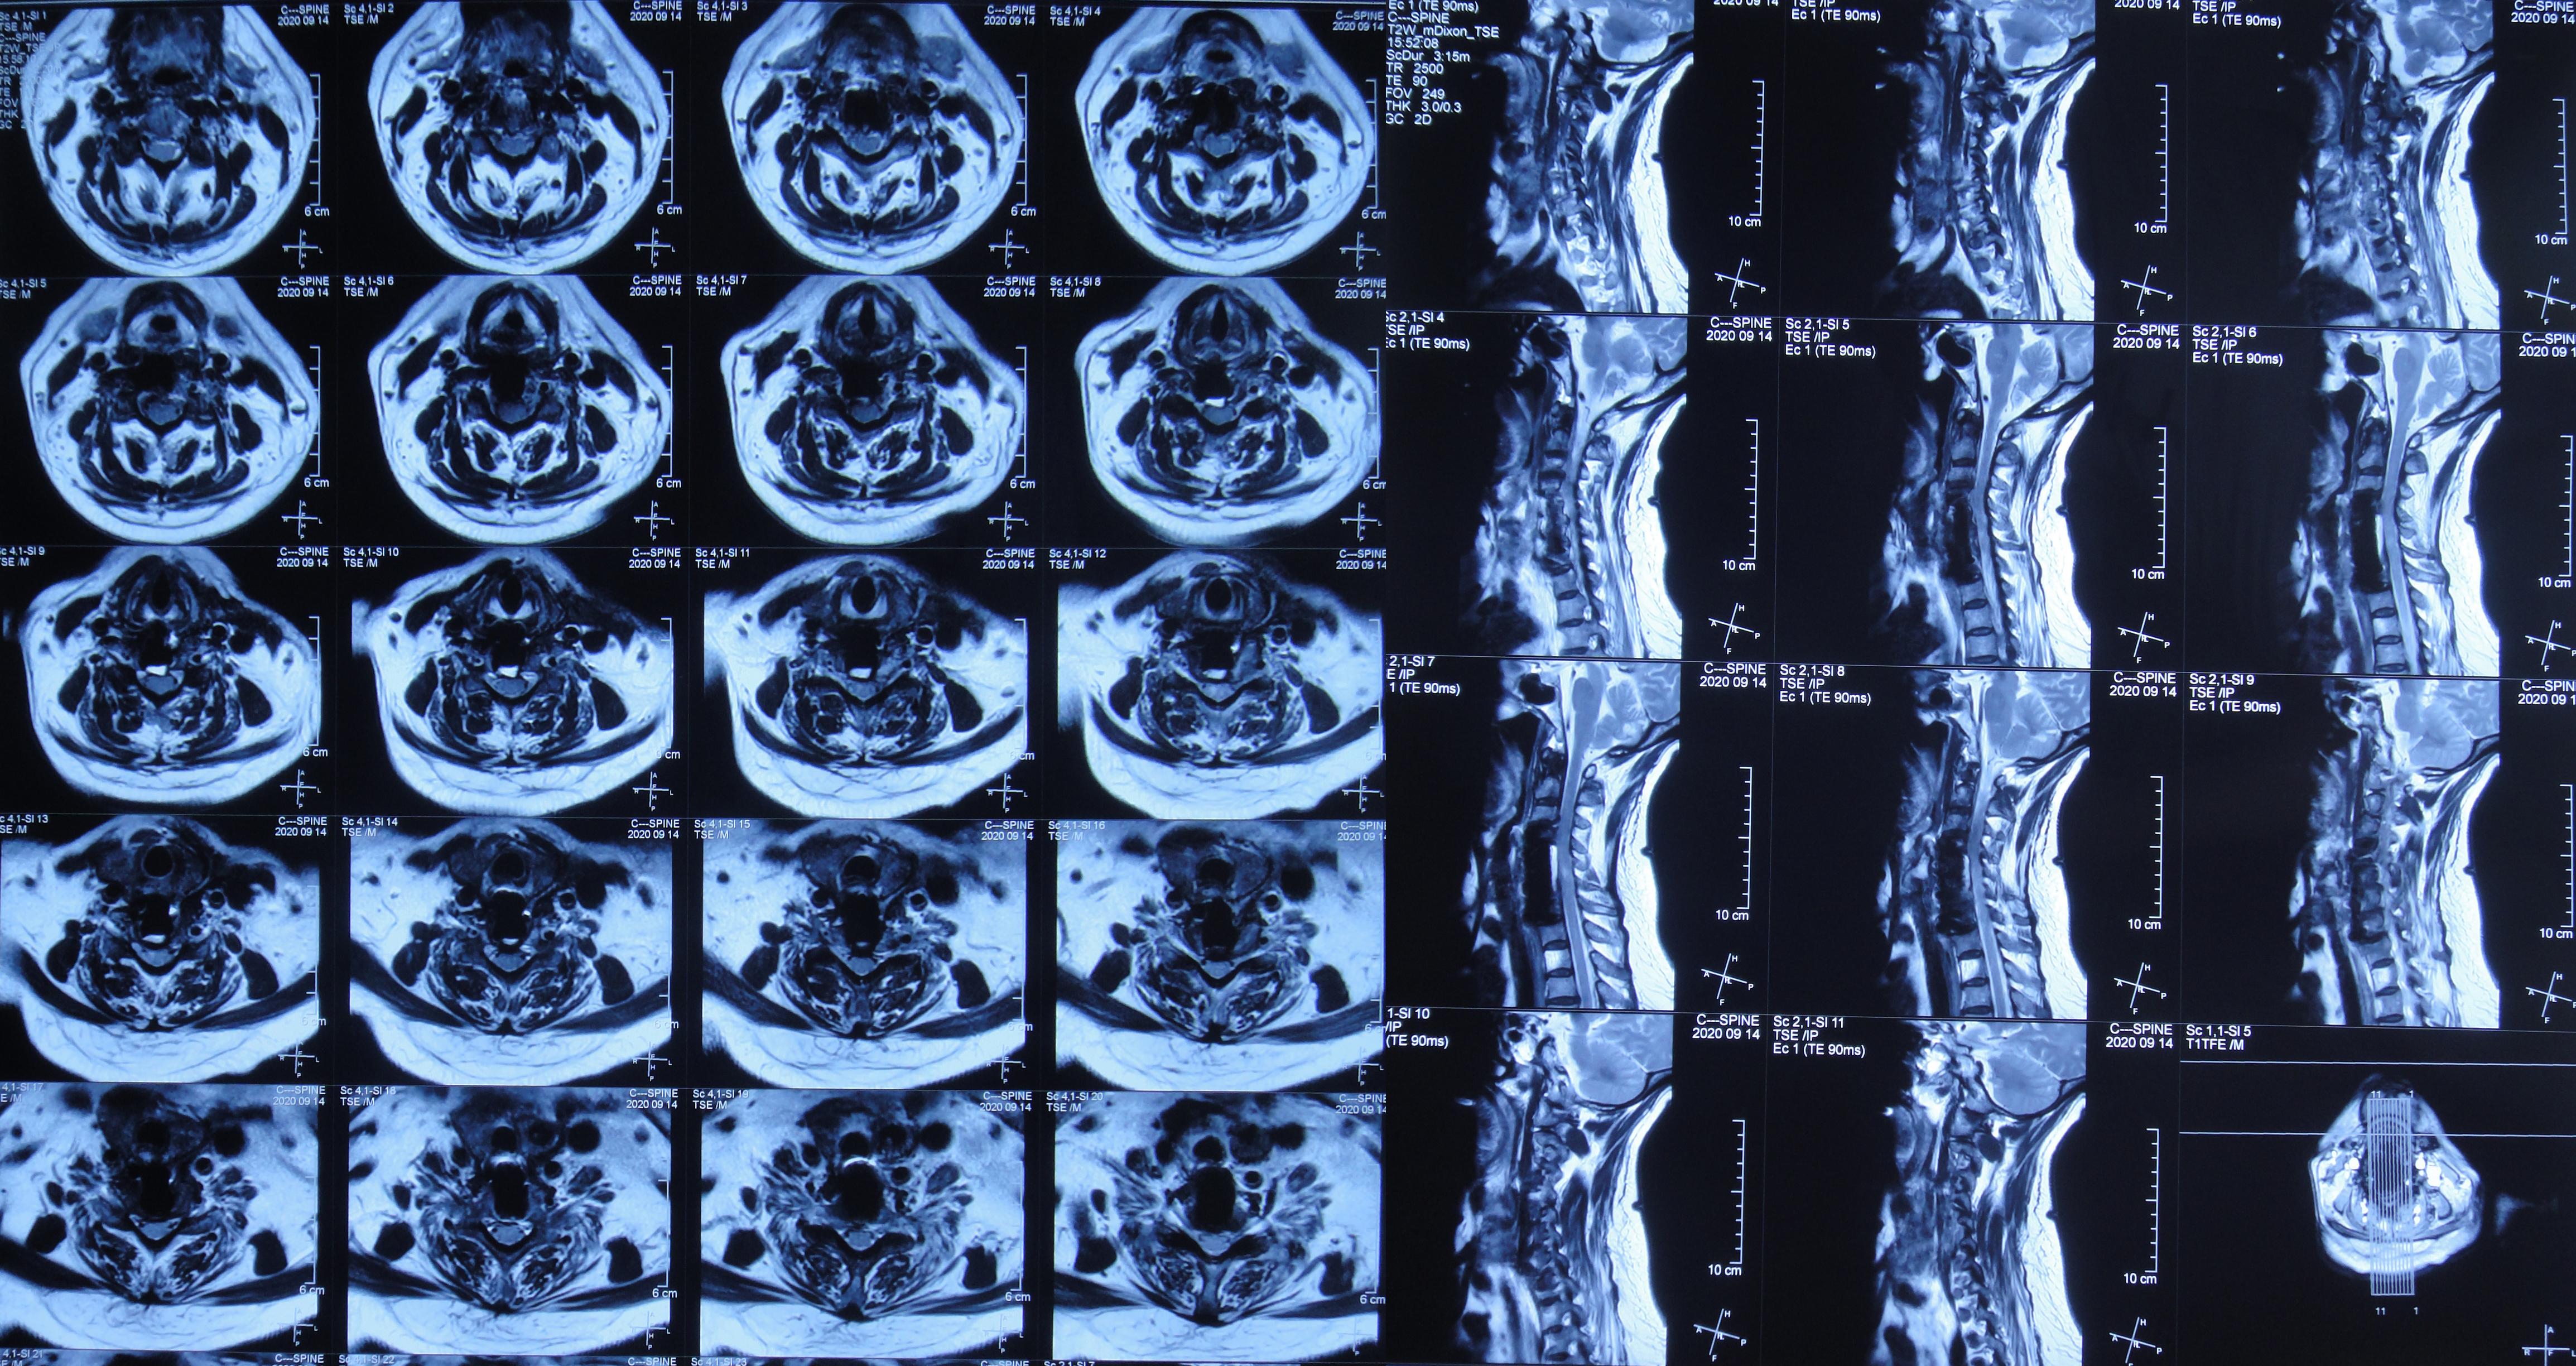

2020年9月14日(入脑脊液科第14天,即脑室外引流术后第11天,即颈椎脑脊液漏修补术后第18天,即第二次颈椎病术后第31天)复查颈部MR示皮下积液已基本消失( 图-13 )。

图-13: 2020年9月14日